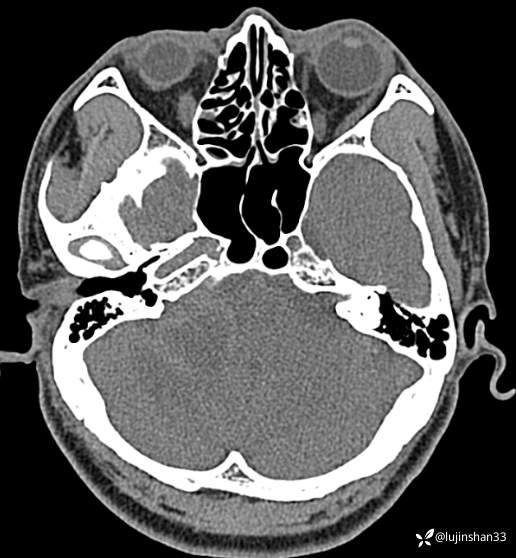

术前CT及MRI

简要病史:患者2020-12月无明显诱因突发眩晕,呈天旋地转伴恶心、呕吐及蝉鸣音样耳鸣,持续约半小时。此后3-4个月内眩晕频繁发作,平均2次/周,眩晕程度较前加重、持续时间延长至每次约40分钟。当时首诊于当地某私人诊所,诊断“肩周炎”,给予口服中药及针灸治疗一段时间后,无明显改善。2021-04月自觉渐进性听力下降但眩晕明显好转。未进一步治疗。2022-06月出现头蒙昏沉伴走路不稳,持续性“蝉鸣音”样耳鸣伴耳闷及渐进性听力下降。2022-07月就诊于XX市第二人民医院耳鼻喉科,行颞骨CT及颅脑MRI检查后提示:听神经瘤(右)。先后又分别就诊于XX省立医院及XX医科大学第一附属医院,诊断同前,均建议上级医院进一步就诊。2022-08月自觉眩晕、耳鸣及听力均较前进一步加重。今为求进一步治疗,2022-08-04就诊我院,门诊以“听神经瘤(右)”收入院。